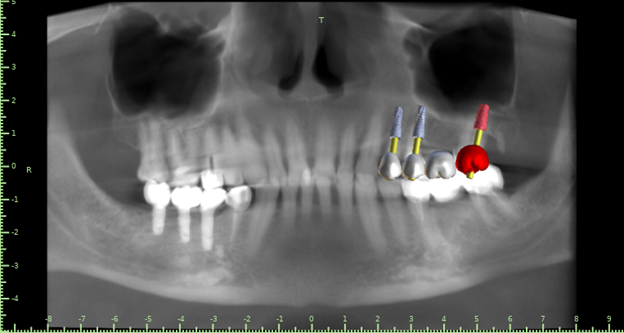

Женька Опубликовано 21 октября, 2021 Автор Поделиться Опубликовано 21 октября, 2021 Хотя если планировать вот так, то вроде и не всё так уж страшно? Ссылка на комментарий

Женька Опубликовано 27 октября, 2021 Автор Поделиться Опубликовано 27 октября, 2021 @Фаик Исламбеков пока только получил согласие пациента на снятие моста, одномоментную установку вот в таких позициях. Буду делать одномоментно, факап может только с 2.7 случиться кмк... в случае чего ушьём и зайдем через 2-3 месяца. 1 Ссылка на комментарий

annda Опубликовано 3 ноября, 2021 Поделиться Опубликовано 3 ноября, 2021 (изменено) Желательно планировать, чтобы коронка верхнего моляра была дистальнее нижней коронки. Щеки могут прикусывать. Хотя, и на своих зубах тут конкретно верхний ряд короче слева, может и обойдется. Изменено 3 ноября, 2021 пользователем annda Ссылка на комментарий

Женька Опубликовано 3 ноября, 2021 Автор Поделиться Опубликовано 3 ноября, 2021 @annda может тогда в бугор дистальный поставить? Но с ортопедией возникнут вопросы тогда... В дистобукальный корень некуда... карман,все дела. А как на снимках хоть в трифуркации можно торкнуть Ссылка на комментарий